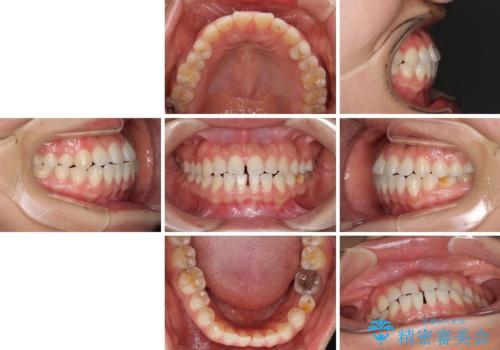

- 上下の前歯の隙間を気にして来院された患者様です。

インビザラインを用い、上下歯列のスペースを閉じていくこととしました。

治療期間中は奥歯がほとんど咬めない状態が続き、食事に大変苦労されました。

最終的には隙間もしっかりと閉じ、奥歯も咬みやすい状態でしあげることができました。